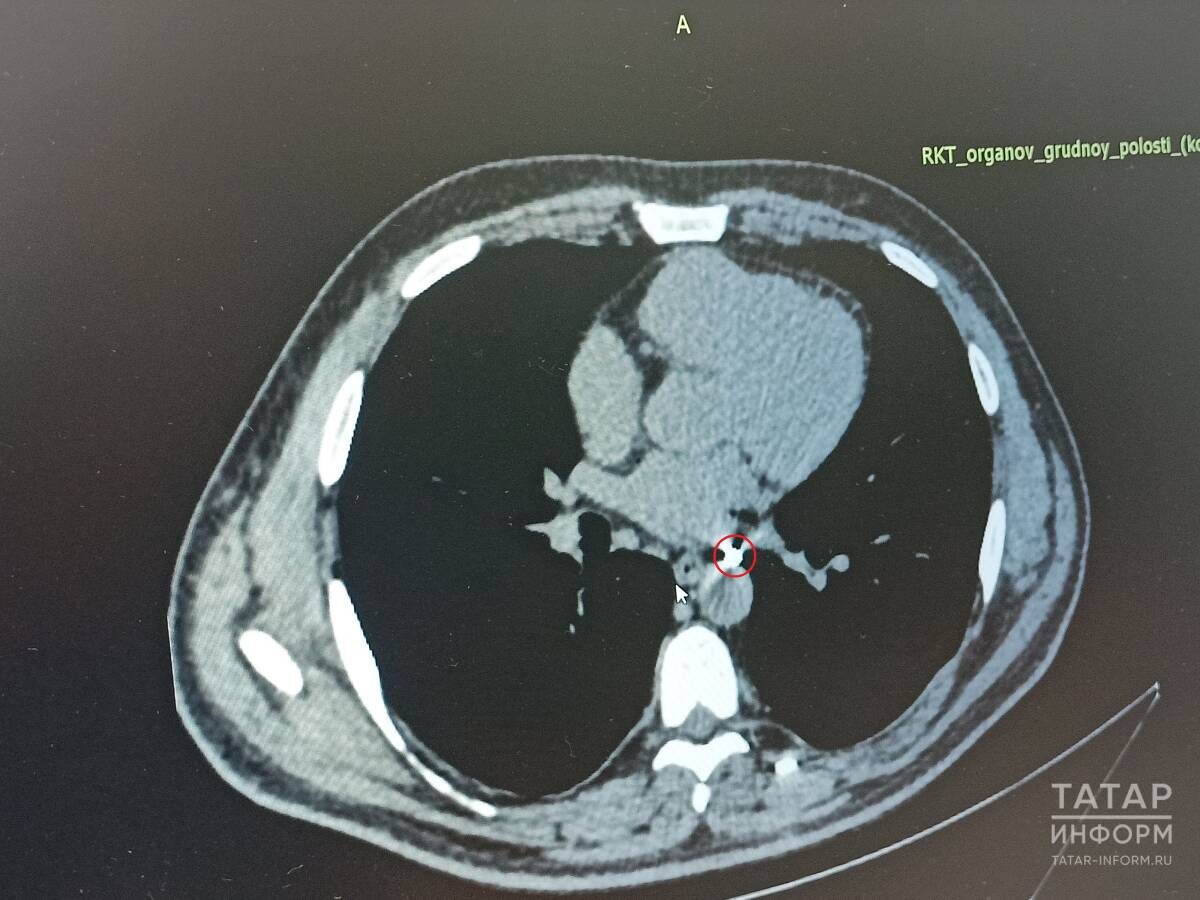

Сложность случая Владимира, объясняют врачи, заключалась в том, что осколок располагался между крупными сосудами – легочной веной и аортой. Учитывая, что ранее он перенес ранение легкого и оно, по словам медиков, приросло к грудной стенке, то сначала необходимо было отделить легкое и только потом доставать осколок.

«Осколок располагался на стенке аорты. К счастью, в сам сосуд не проник. Мы успешно удалили его. Сейчас он ничем не угрожал здоровью, но в будущем мог вызвать пролежень и кровотечение», – подчеркнул врач.